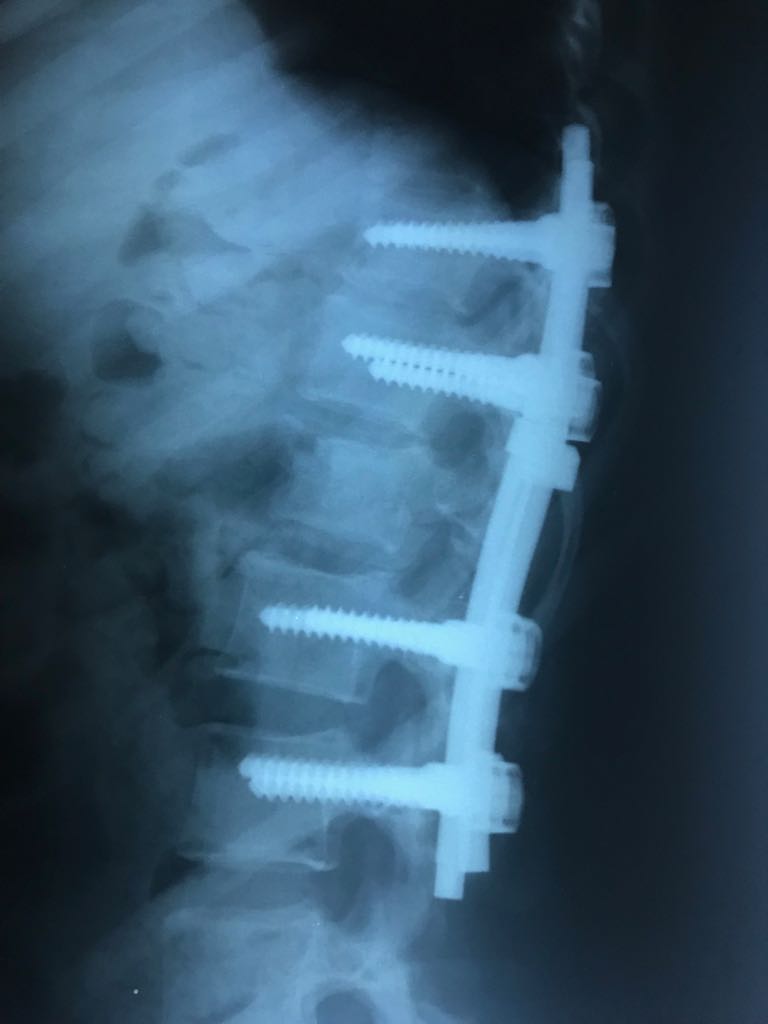

Ameliyat Sonrası